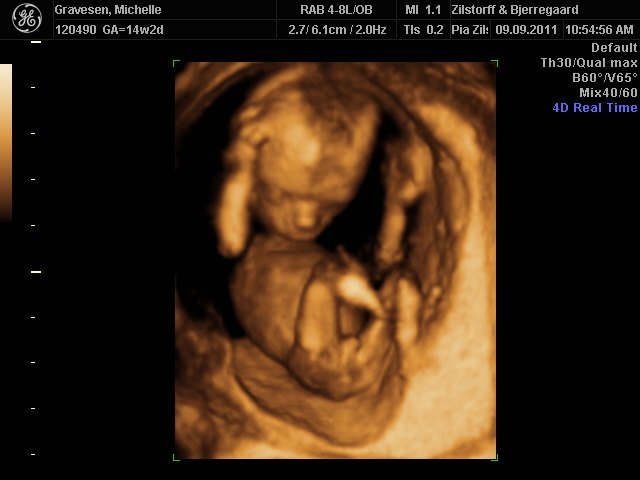

prøver lige at sætte to billeder ind. den ene fra 1. kønsscanning den anden fra 2. kønsscanning.

Hvad synes i? Udvikler barnets sig i ret af dreng eller pige?